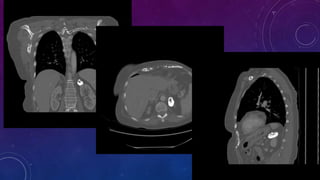

HYPERDENSE SPLEEN- THOROTRAST?

Thorotrast is a radioactive radiographic contrast

agent containing thorium dioxide first produced in

Germany in 1928 and was in use until the 1950s. It

was used primarily for cerebral angiography, and 90%

of the estimated 50,000-100,000 patients who

received it were studied for this purpose.

• Large rim calcified cyst in the spleen, likely

benign. This could be secondary to previous

trauma.